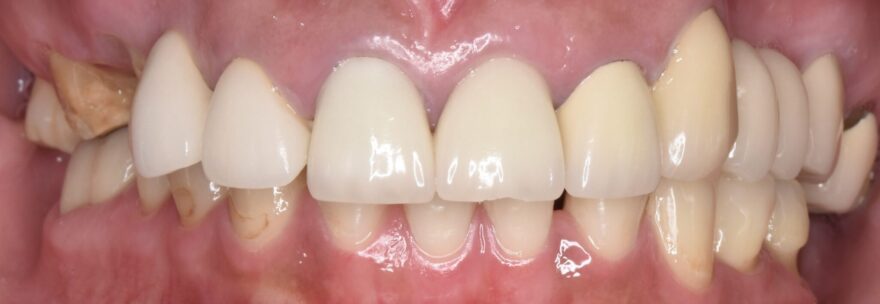

奥歯がなくて噛めない上に顎まで痛い:50代女性

AFTER

困った時に、その場限りの治療でしのいできたものの、いよいよ顎まで痛くなってしまい、当院を受診されました。

7本のインプラント治療と18本のセラミック治療で、顎関節とのバランスまで考慮した機能的な噛み合わせを再建しました。